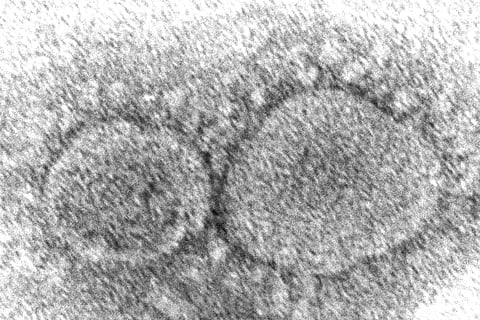

Washington [US]: During a recent study, an international team of scientists identified antibodies that neutralize omicron and other SARS-CoV-2 variants.

These antibodies target areas of the virus spike protein that remain essentially unchanged as the viruses mutate. The study's findings were published in the journal Nature.

The omicron variant has 37 mutations in the spike protein, which it uses to latch onto and invade cells. This is an unusually high number of mutations. It is thought that these changes explain in part why the variant has been able to spread so rapidly, to infect people who have been vaccinated and to reinfect those who have previously been infected.